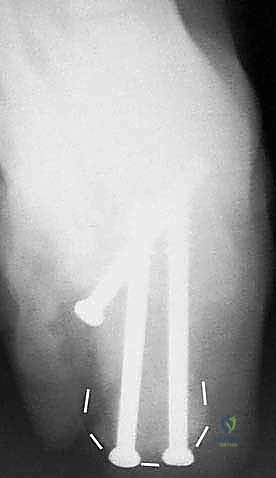

- دمج المفصل تحت الكاحل (Subtalar Arthrodesis):

في الغالبية العظمى من حالات سوء الالتئام، يكون المفصل تحت الكاحل قد تدمر تماماً بسبب الخشونة والاحتكاك. الحل الجذري والنهائي للألم هنا هو "دمج" أو "تثبيت" هذا المفصل. يقوم الدكتور هطيف بتنظيف الغضاريف التالفة بالكامل، ووضع العظام في وضعها التشريحي الصحيح، ثم تثبيتها باستخدام براغي معدنية قوية جداً (Screws) لتلتحم وتصبح عظمة واحدة صلبة خالية من الألم.